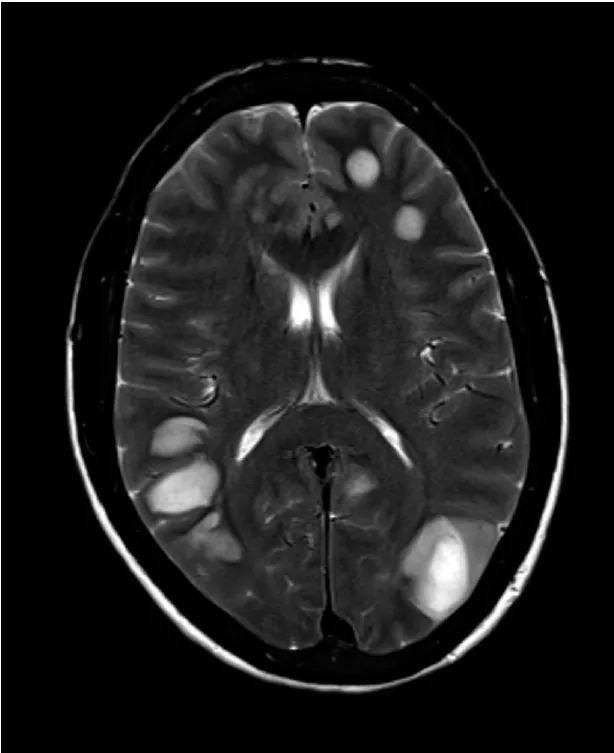

Uma causa incomum de hematúria glomerular intermitente!

Uma causa incomum de hematúria glomerular intermitente!

Hematúria pós infecção, caso clínicos para auxiliar no entendimento de causas glomerulares comuns e raras...